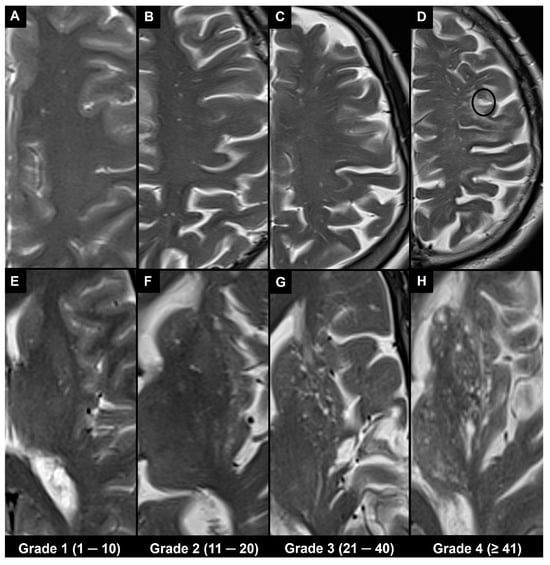

4.1. Visual Scoring